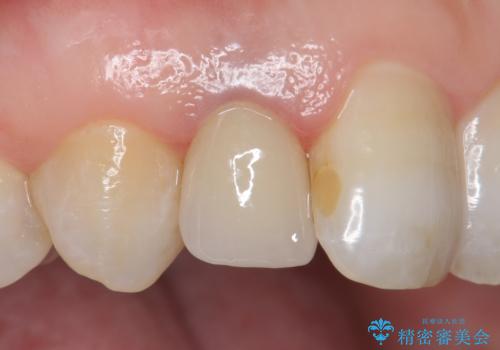

- 右上2番目の歯の変色が気になるといらっしゃった方の症例です。

再根管治療終了後、オールセラミッククラウンによる補綴を行いました。

今回用いたオールセラミッククラウンはジルコニアフレームという白い素材の上にセラミックを盛っているため、審美性が非常に高いのが特徴です。

また、ジルコニアは人工ダイヤモンドの材料にも使われているほど高い強度を持っており、そのためオールセラミッククラウンは審美性だけでなく、奥歯やブリッジの補綴も可能とするクラウンです。